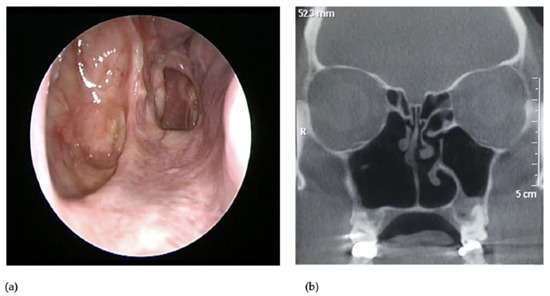

3. Presentation

4. Management